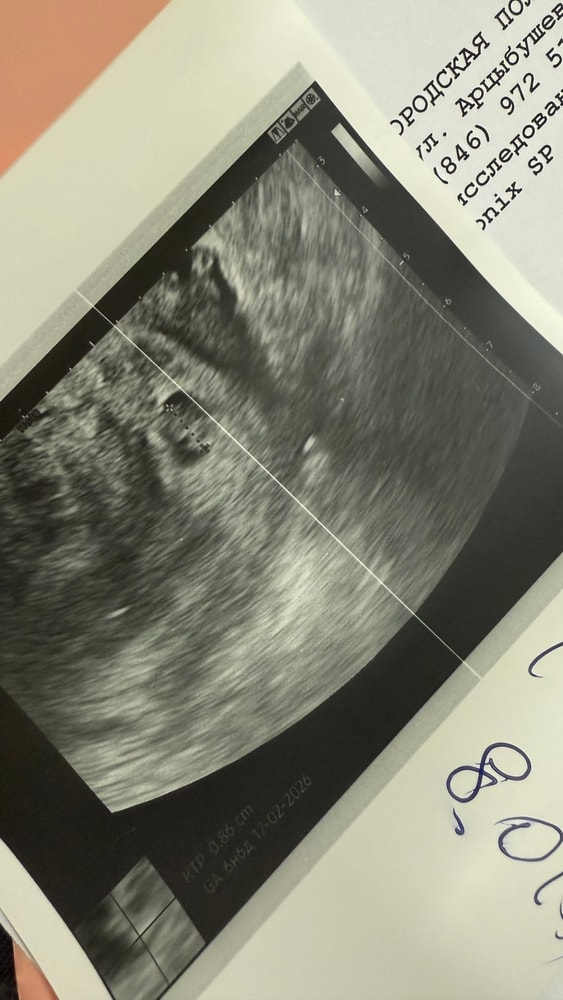

Жёлтое тело здесь не главное,у вас пя 8,4,а эмбрион 8,6,т.е они одного размера и жм у вас уже нет,но сердцебиение при этом есть, очень странное УЗИ

Переделайте УЗИ,это очень странное какое -то вообще пя у вас меньше чем эмбрион,хотя эмбрион находится внутри пя,а фото есть с УЗИ со снимком ?

AFINA , да,но для благополучной беременности в пя место должно быть, минимальная разница 5 мм между пя и ктр и она должна сохраняться,у вас вообще разницы нет,они одинаковые,пя задавит эмбрион,с вашим эмбрионом 8,6 пя должно минимум быть 14 мм хотя бы

AFINA , с такими данными да,к сожалению шансов нет,странно что ещё живой,сколько наблюдала с разницей в 1-2 мм с пя уже замирали,у вас ещё возможно ошиблись в замерах,так как немного УЗИ странноватое, поэтому не буду делать прогнозов,может у вас и пя нормальное,смотря ещё с какого ракурса фоткали